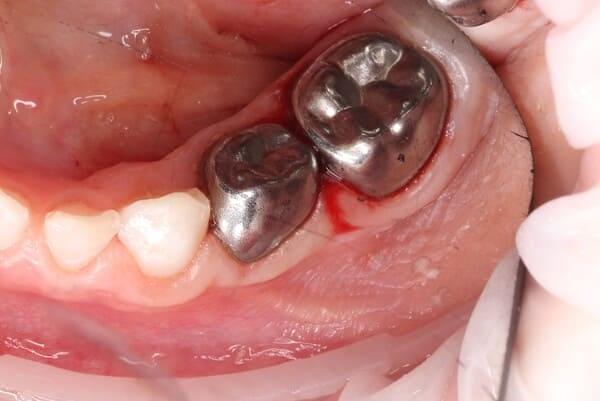

Маленька дівчинка двох років. Лікування проводилось в умовах анестезіологічного забезпечення. Завдяки злагодженій команді анестезіологічної та стоматологічної команди було проведено складне та об’ємне лікування. Було проведено лікування карієсу, герметизація фігур та лікування пульпіту (запалення «нерва») передніх зубчиків з відновленням естетичними коронками. Також бічні зубчики відновлені коронками металевими. Коронки можна комбінувати: на бічні ділянки встановлювати металеві, а на передні зубчики естетичні, щоб забезпечити оптимальну функцію та естетику.

Дівчинка 4 роки. Лікування проведено в анестезіологічному забезпеченні через значний обʼєм ураження жувальних зубів зубів прийнято рішення їх відновлення за допомогою металевих коронок, що допоможе зубам ефективно виконувати свої функції та позбавити дитину від болю.

Дівчинка 4,5 років скаржилась на біль в нижньому зубі справа. В зв’язку з високою складністю процедур і значним об’ємом лікування (8 зубів) та після невдалої спроби лікування в звичайному режимі було прийнято рішення про лікування в умовах анестезіологічного забезпечення. Видаленно запалену пульпу (“нерв”) та проведено лікування каналів нижнього зуба ліворуч, цей та сусідні зуби покриті металевими коронками через значний об’єм ураження. Проліковані всі зуби, які потребували допомоги, щоб в майбутньому уникнути болю, дискомфорту та поширення інфекції. Через три години лікування дівчинка може комфортно жувати і не відчувати болю і дискомфорту.

Металеві коронки. Біленко Наталія.

Коли карієс вражає одразу декілька поверхонь зуба, то на допомогу приходять стандартні дитячі коронки. Вони повністю відновлюють жувальну функцію зуба, а також профілактують вторинний карієс. В даному випадку до нас звернулися батьки хлопчика 6-ти років, коли помітили карієс на контактній поверхні. Ми пролікували нерв зуба, відновили його початкову форму і виконали постановку стандартної металевої коронки. Це допоможе зберегти зуб до його фізіологічної зміни, яка відбудеться ще не скоро.

Металеві коронки. Біленко Наталія.